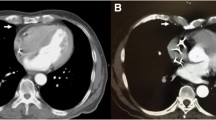

The present study aims to determine the influence of two different coronary surgical revascularization techniques featuring skeletonized BIMA as T-graft (Fig. 1) on the postoperative outcome including atrioventricular valve function.

We reviewed 204 consecutive patients who underwent first time CABG for 3v-CAD with BIMA T-Graft as sequential grafting (C-T-BIMA) or with BIMA as T-Graft for the revascularization of the left-sided coronary arteries and an aorto-coronary graft for the right-sided vessels (L–T-BIMA + R-CABG, Fig. 1).